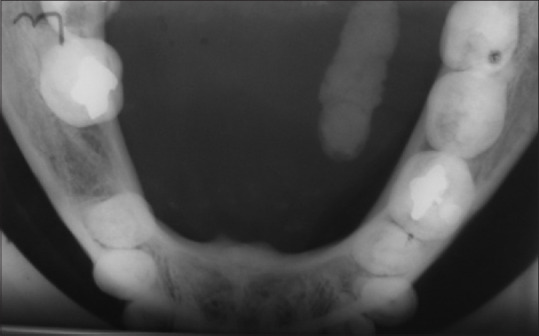

The major salivary glands (parotid, submandibular, and sublingual) are most frequently obstructed by calculi within the salivary gland, or more uncommonly, by ranulas. Despite the well-defined clinical and radiographic diagnostic features, sialolithiasis may sometimes be confused with sialadenitis and ranulas, especially when encountered in general dental practice. We, therefore, present a case that illustrates this diagnostic dilemma to highlight the salient features of all three conditions. A 28-year-old female presented with a history of a submandibular swelling for 8 months. On intraoral examination, a bluish sublingual swelling was identified at the left side of the lingual frenum, causing a slight elevation of the tongue. The preliminary diagnosis was of a ranula; however, the clinical history suggested sialolithiasis. A hard structure was palpated in the submandibular gland, and a mandibular occlusal film revealed a large ductal sialolith. Sialolithotomy was performed under local anesthesia, and a single 7.2 mm stone was retrieved. The postoperative follow-up period was uneventful, with good healing and restored normal salivary flow. Despite the fairly clear clinical and radiographic diagnostic criteria suggestive of sialolithiasis, the bluish-tinged swelling of the floor of the mouth prompted the examining dentist to provisionally diagnose a ranula. Sialolithiasis is a common obstructive condition of the salivary gland encountered in the dental setting. Despite the clinical and radiographic features usually guiding the correct diagnosis, it can be a challenging diagnosis for less experienced dentists, who must always carefully consider the history, clinical, and radiographic findings.